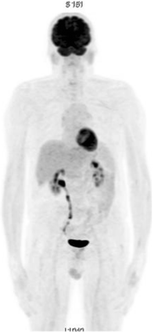

A 55-year-old man presented with a polydipsic syndrome and showed severe hypercalcemia. Medical history, laboratory tests and CT scan ruled out any malignant or iatrogenic cause. Granulomatosis was considered likely. There was no mediastinal lymphadenopathy and histology of the minor salivary glands was normal. A PET/CT scan showed strong 18F-FDG uptake in all skeletal muscles, suggesting myositis (Fig. 1). The CPK rate was normal. MRI of the legs showed a STIR-weighted hypersignal and a T1-weighted hypersignal of every muscle (Fig. 2). Muscle biopsy revealed an intramuscular non-necrotizing giant cell granuloma. Diffuse sarcoidosis myopathy was considered likely because of the absence of other granulomatous conditions. The evolution was rapidly favourable after glucocorticoid treatment. The patient completely recovered and a PET/CT scan showed a complete metabolic response (Fig. 3) at 3 months.